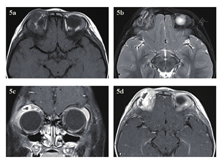

急诊入院者16例,6例患者行了MRI检查,主要为CT发现絮状密度影等感染征象、未发现异物影的,2例MRI发现异物影(图4a~d)。早期入院者7例,5例行了MRI检查(包括3例CT未发现异物的患者),其中3例发现异物影。其主要表现为:T1WI呈等信号或低信号,T2WI呈等信号,增强时中央无强化影,周边强化(图5a~d);中晚期入院者19例,16例行了眼眶MRI检查(未行MRI检查的为CT明确发现异物的)。其中15例患者发现异物影(93.8%),主要表现为:T1WI呈低信号,T2WI呈等信号或混杂高信号表现,增强时多表现为病灶中央无强化影(异物,不强化),周边明显强化(冠状位的典型表现为环状增强)(图6a~d)。